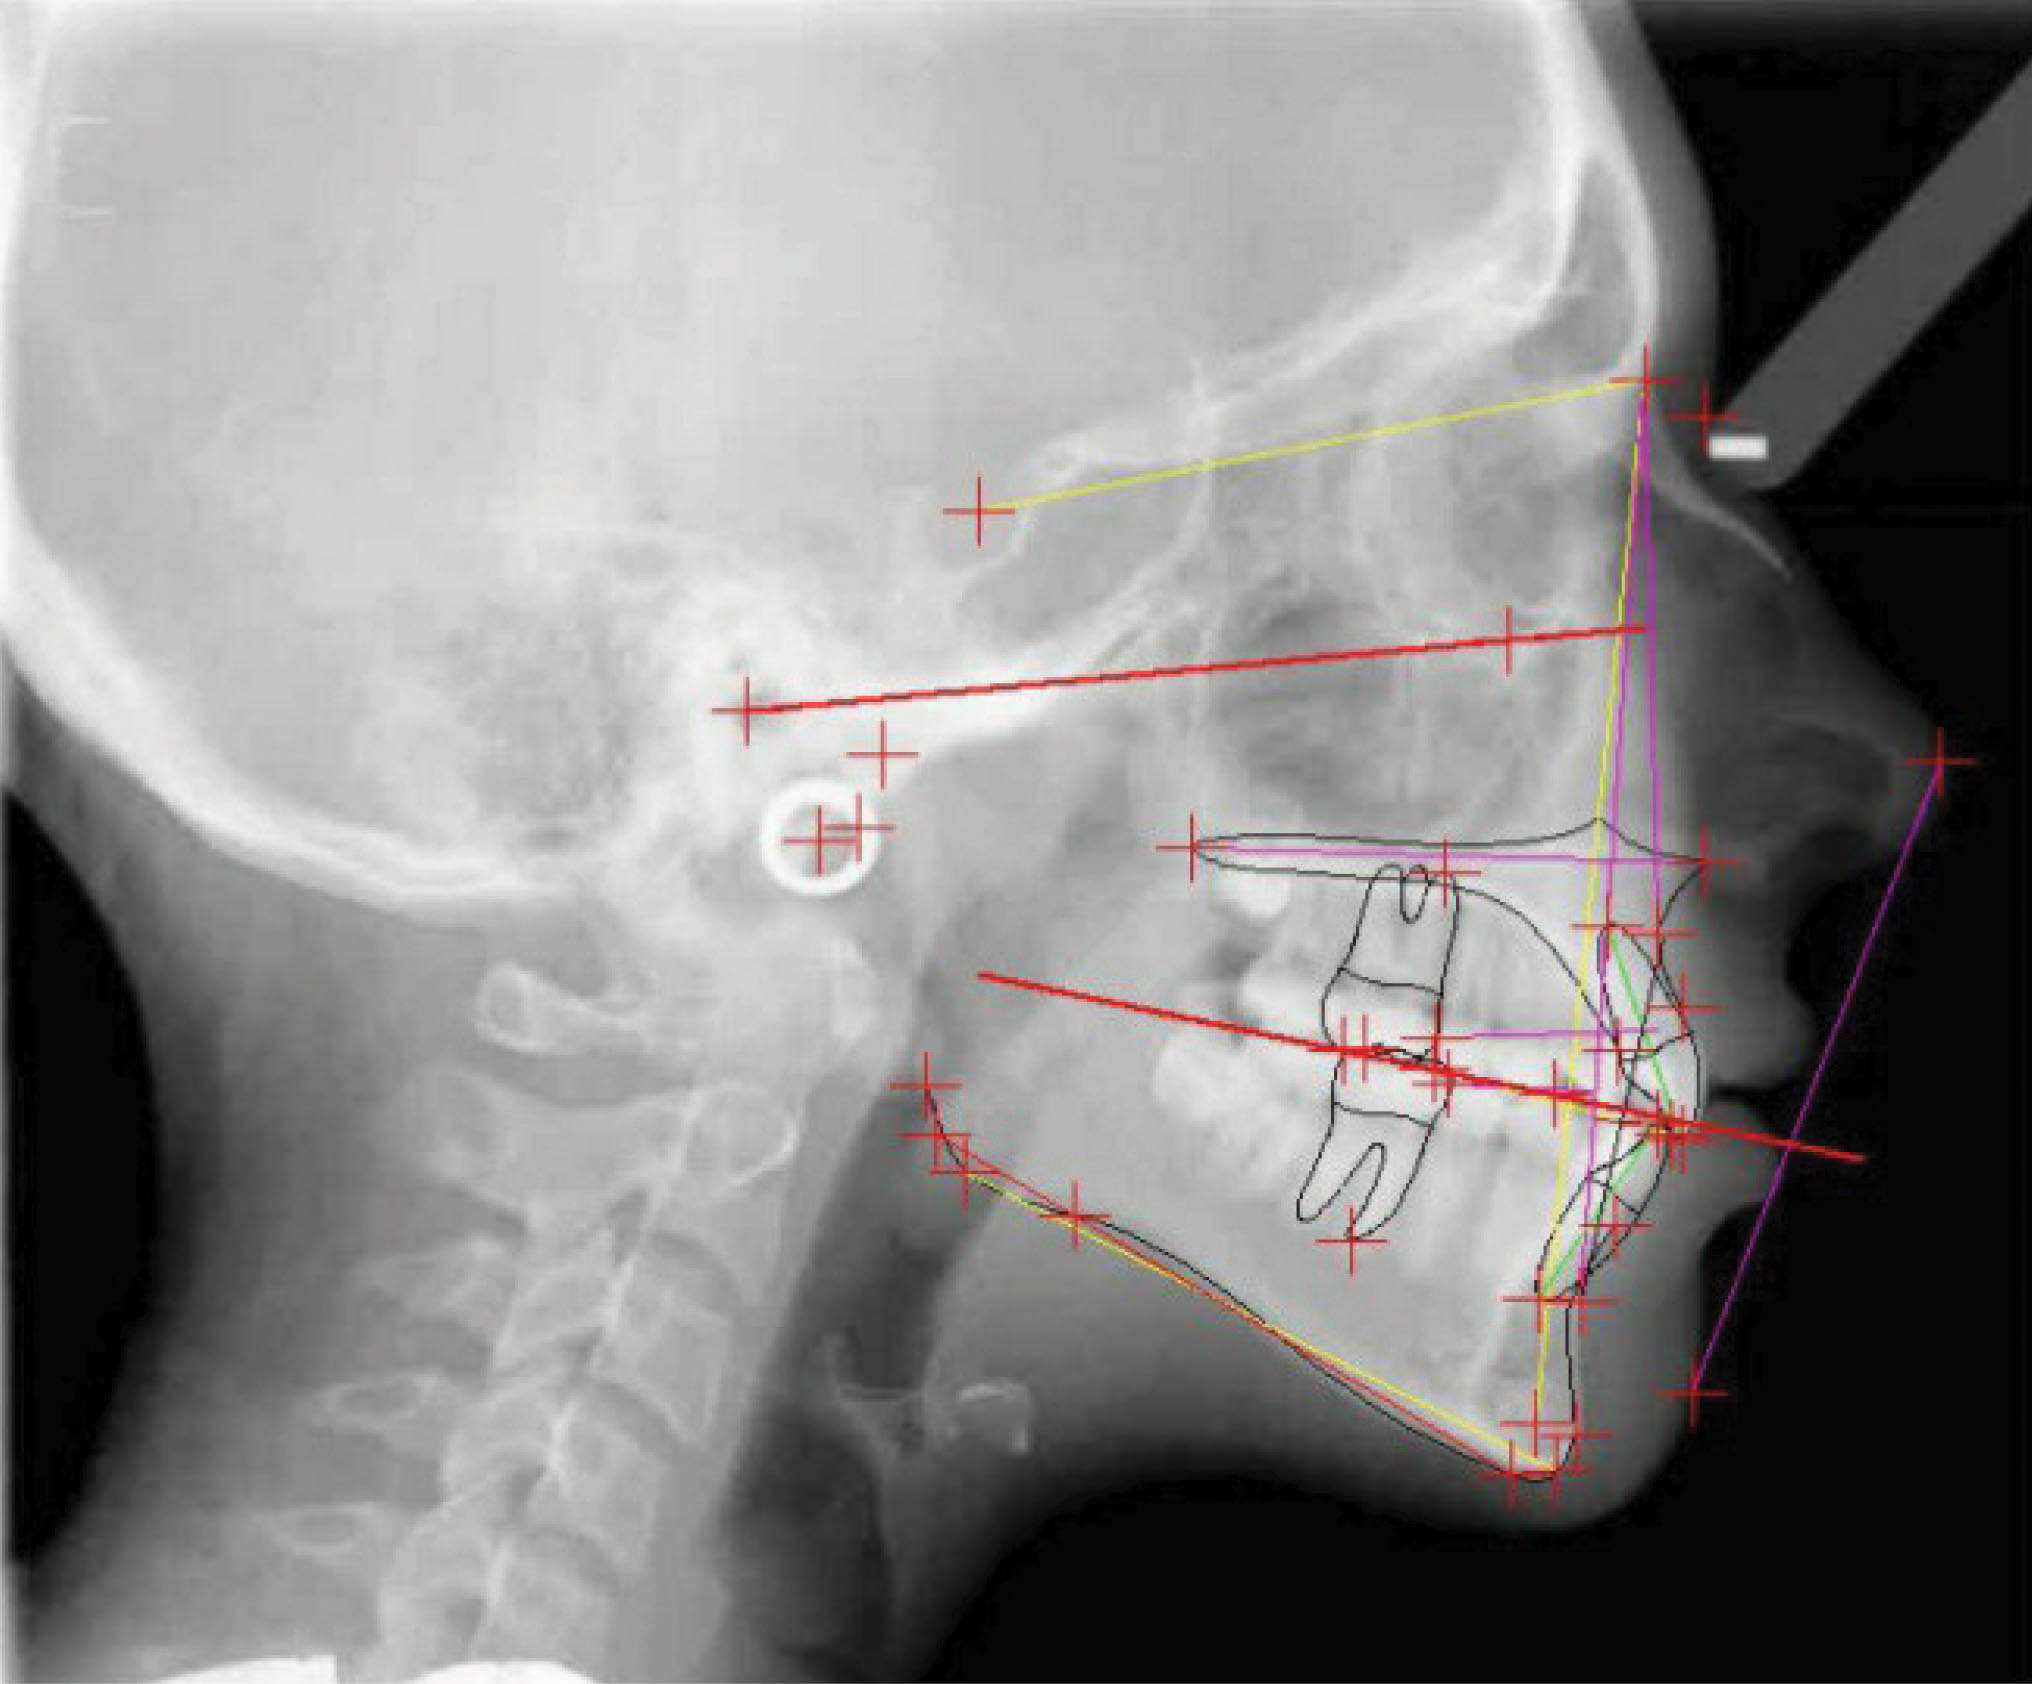

با سوپرایمپوز کردن لترال سفالومتری در شکل 35-6 شاهد سه درجه پروترود شدن انسیزورهای پایین هستیم. ارتفاع عمودی ثابت ماند و کنترل خوبی در حفظ زاویه پلن مندیبل داشتهایم. رادیوگرافی OPG پایان کار (شکل 36-6) طبیعی است. مدت نگهدارنده ۳۰ ماه بود و همه چیز خوب حفظ شده است (شکل 37-6).

شکل 35-6

شکل 36-6

شکل 37-6

شکلهای 33-6 و 34-6 نتایج درمان را نشان میدهد. قوس فکی کاملاً مرتب شده است. عرض بین کانینی حفظ شده، اکستروژن نسبی لترال بالا را داریم و به نتایج زیبایی و فانکشنال خوبی رسیدیم.